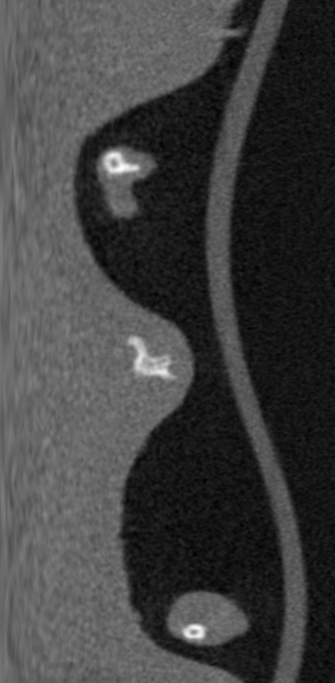

结果贴上

原图

转化成极坐标系

极坐标系转化为直角系

可以看到经过转化,内切圆内区域并没有发生什么变化,内切圆外区域又没什么用(差别是因为两次转化造成的),证明这个计算过程是可行的。代码水平一般将就看吧。